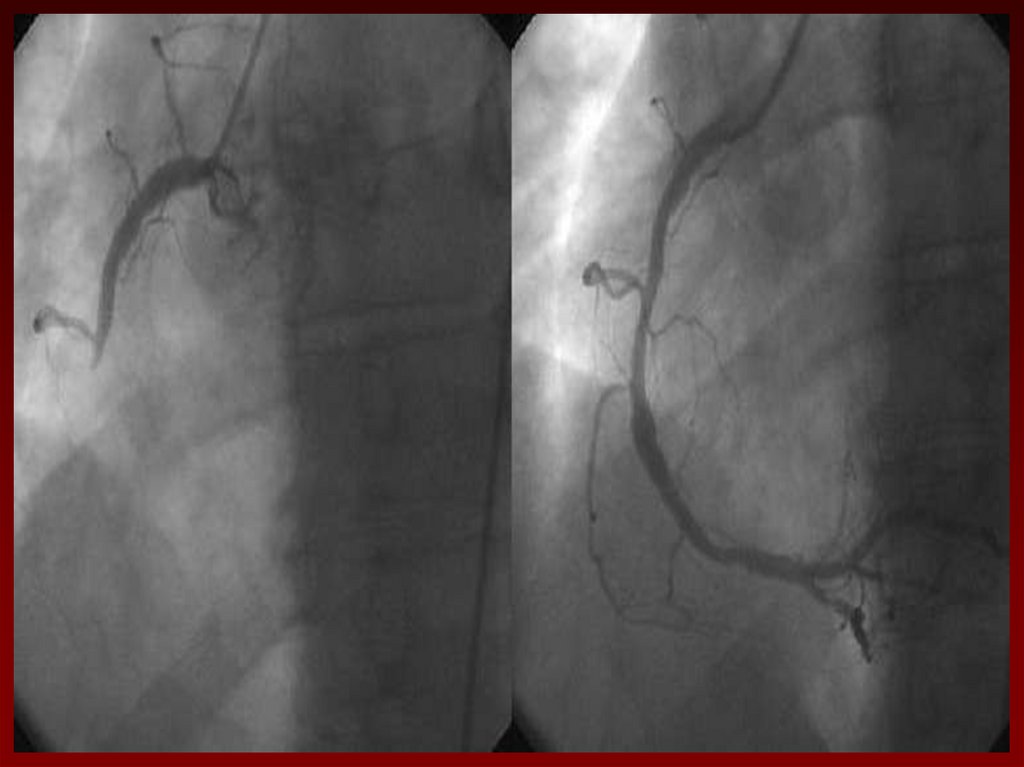

45. КОРОНАРОГРАФИЯ

• Дает информацию о

наличии стенозирующих

изменений коронарных

артерий и их тяжести.

• Пациенты с

многососудистым

поражением и со

стенозом ствола левой

коронарной артерии

имеют более высокий

риск серьезных

осложнений

заболевания.